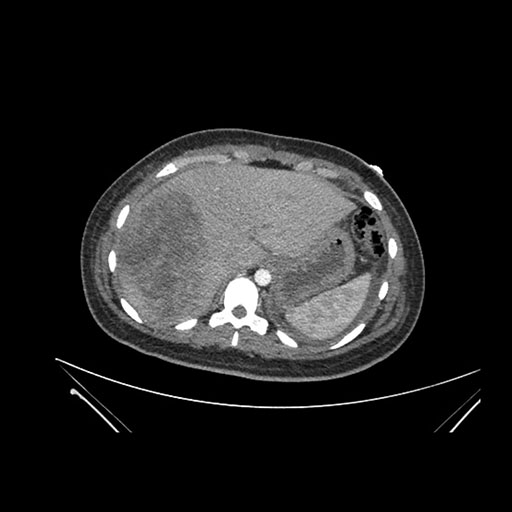

Axial Arterial

Axial Venous